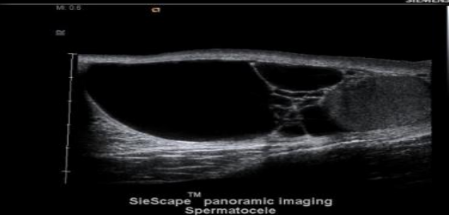

spermatocele

cystic dilation of the efferent ductules of epi and always in epi head

__________________ are seen more often following a vasectomy

spermatoceles